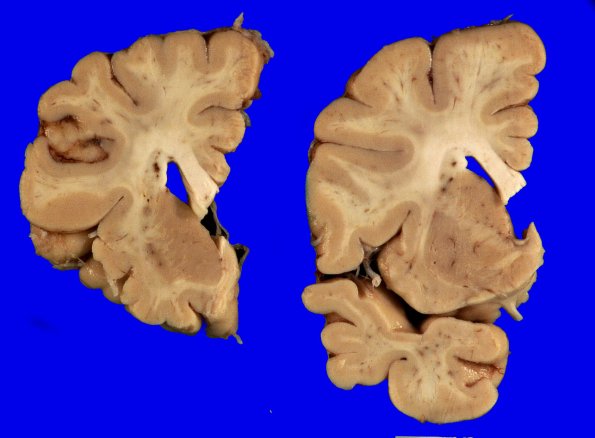

5A4 (Case 5) Gross_4

There is modest atrophy in the frontal lobe but more substantive change in the temporal at this level.